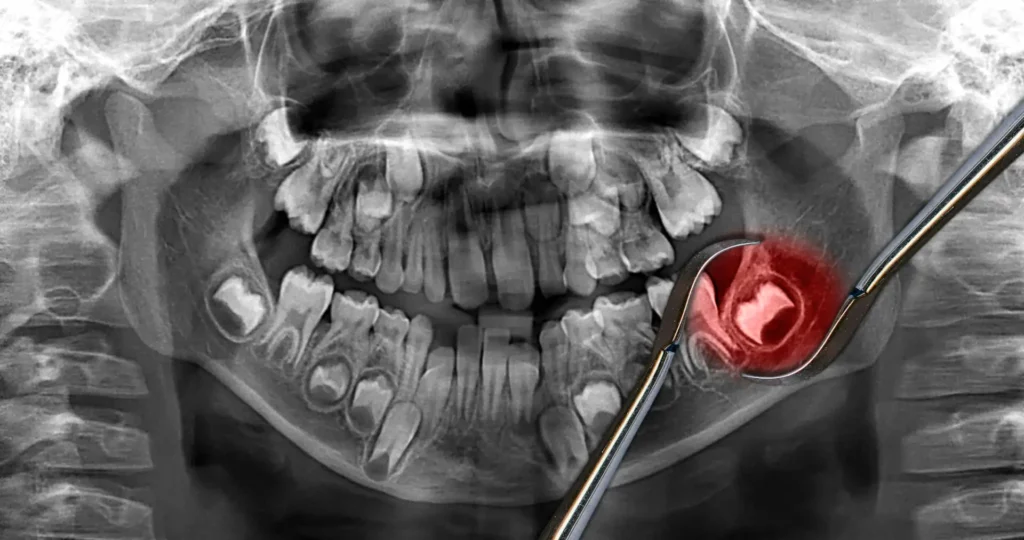

Before teeth removal, your dentist will take X-rays to determine the position of your wisdom teeth and assess whether they need to be removed. Your dentist may refer you to an oral surgeon if your wisdom teeth are impacted (stuck under the gum).

Wisdom tooth extraction involves numbing the area with local anesthesia to prevent discomfort during the procedure. If the tooth is impacted or difficult to reach, the dentist may need to make a small incision in the gum to access the tooth. In some cases, the tooth may be broken into smaller pieces for easier removal. Once the tooth is extracted, the area is cleaned, and stitches may be placed to help the gum heal. After the procedure, patients are given instructions for aftercare, including managing any pain or swelling and promoting proper healing.

You will be given local anesthesia to numb the area around your wisdom teeth during wisdom teeth removal. You may also be given sedation to help you relax. The dentist or oral surgeon will incise your gum tissue and remove the wisdom tooth. In some cases, the wisdom tooth may need to be cut into pieces before it can be removed.